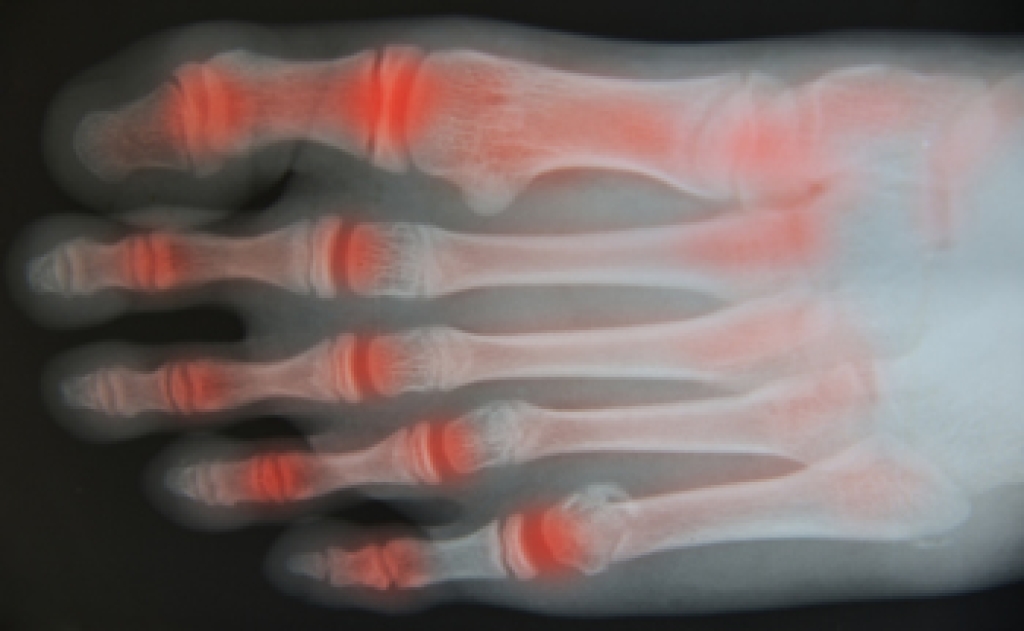

Hammertoe is a foot deformity that occurs due to an imbalance in the muscles, tendons, or ligaments that normally hold the toe straight. It can be caused by the type of shoes you wear, your foot structure, trauma, and certain disease processes.

- Certain Diseases – Arthritis and diabetes may make you more likely to develop hammertoe